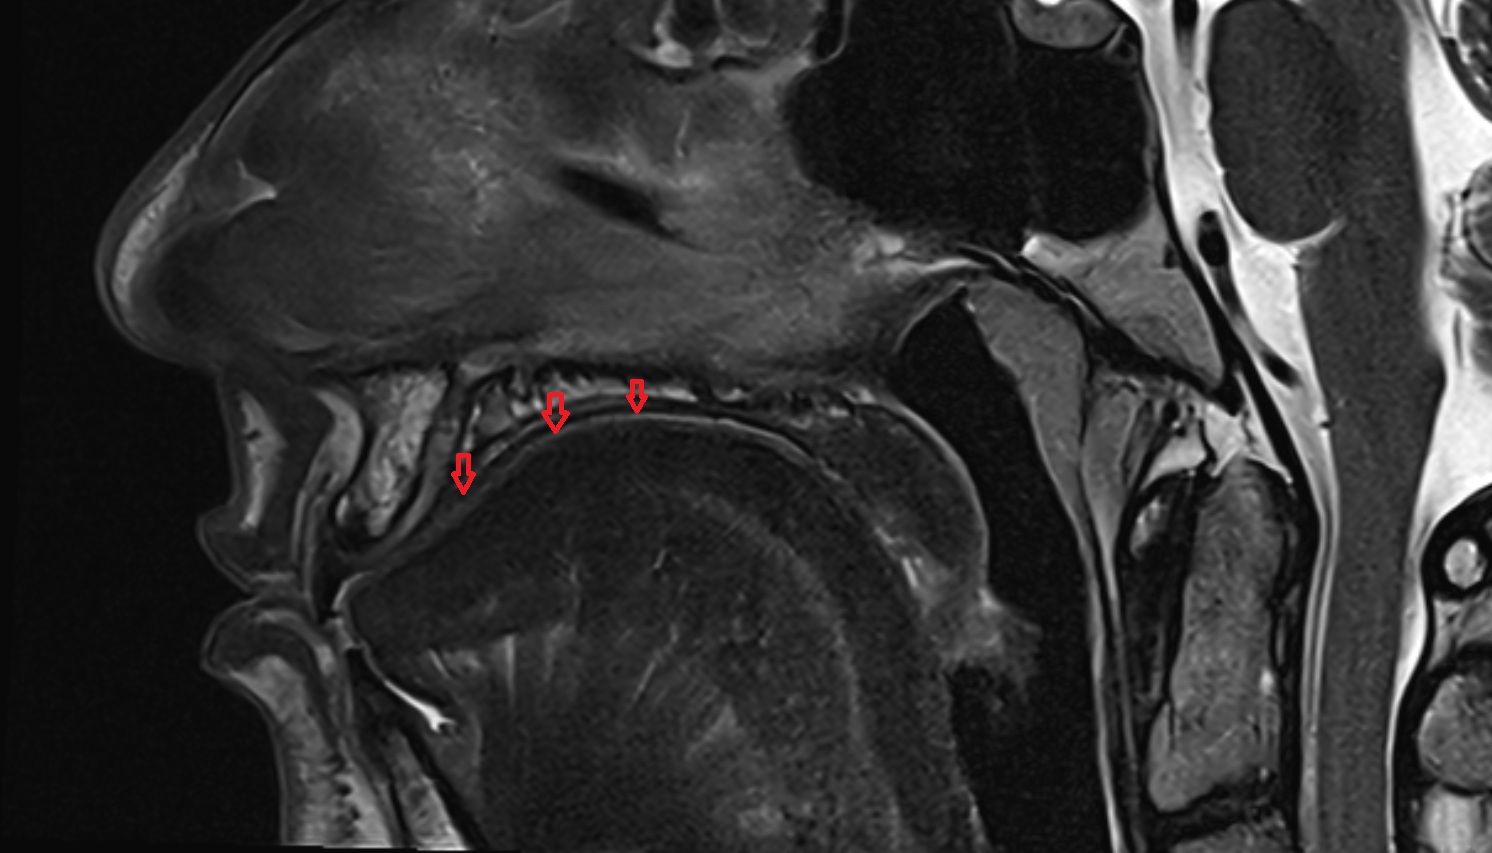

- Temporomandibular joint

- Articular disc of temporomandibular joint

- Articular eminence

- Mandibular condyle

- Mandibular fossa